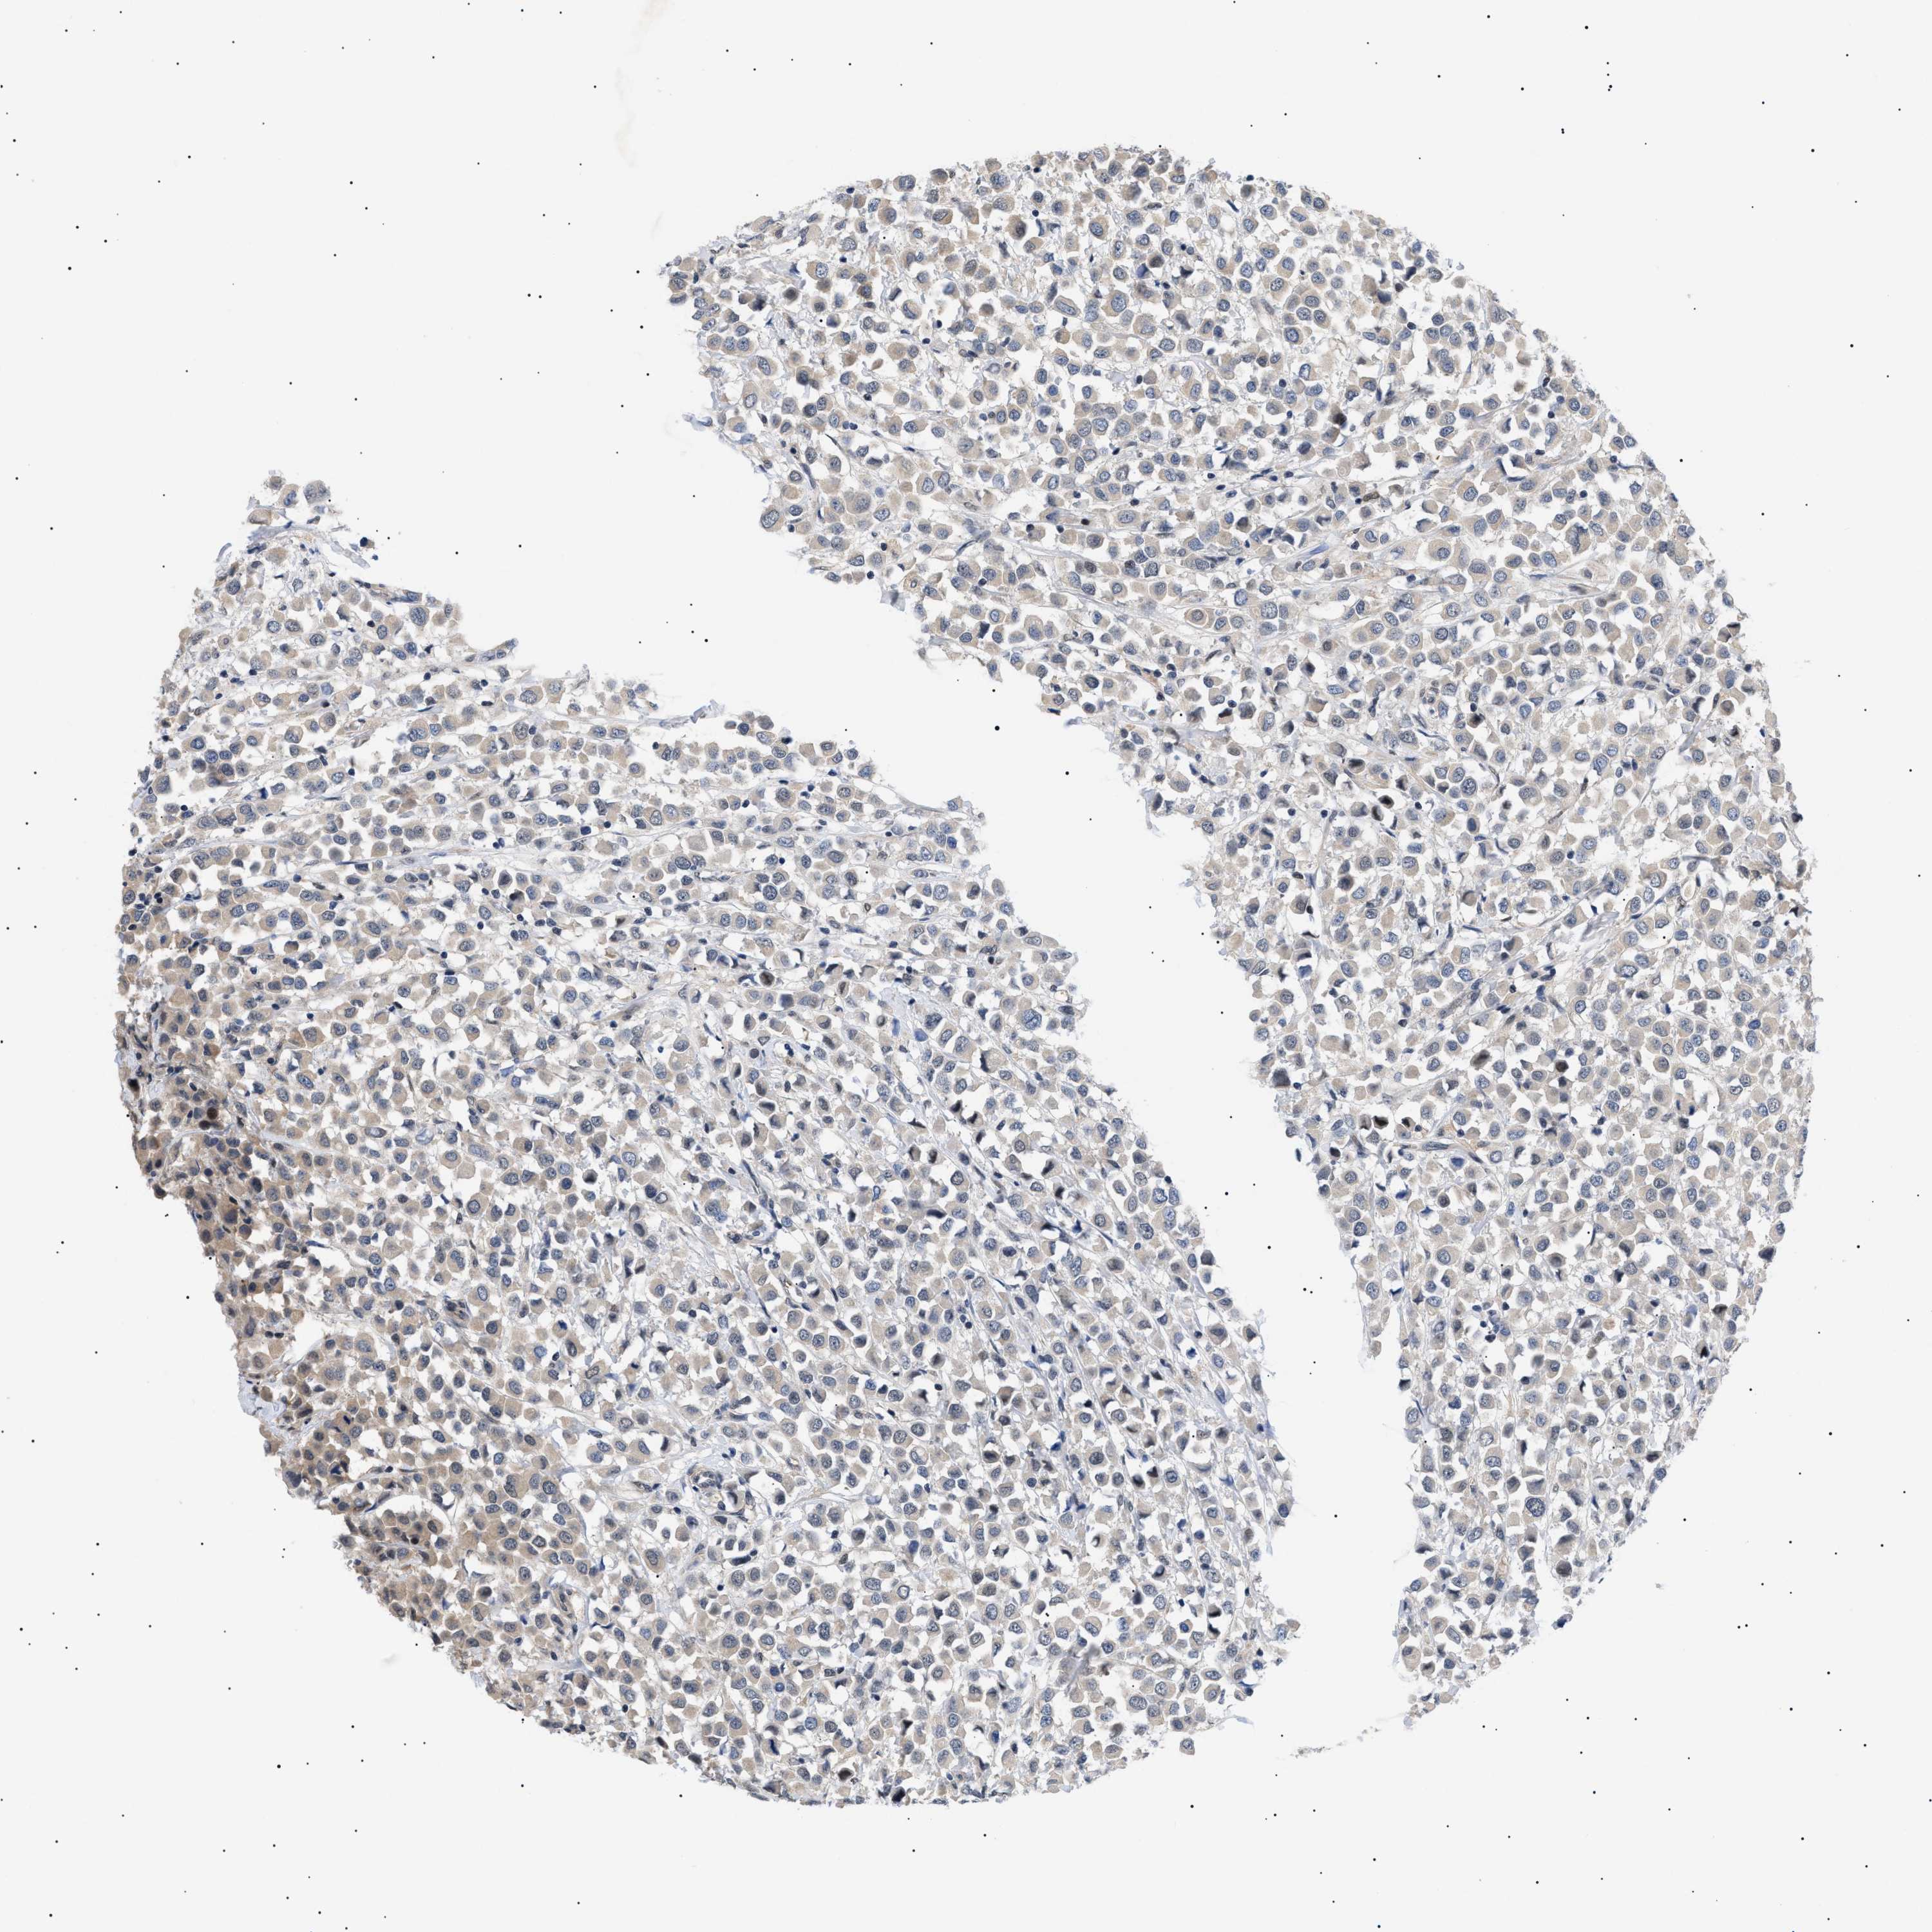

BRCA TCGA BRCA VALIDATION PROTEIN EXPRESSION